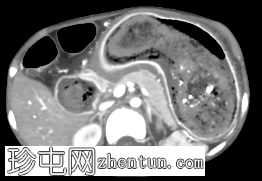

冠状位增强扫描(门静脉期)

胃腔内可见巨大肿块,内含斑驳状软组织、气体和高密度灶,延伸至幽门、十二指肠和近端空肠(长发公主综合征)。十二指肠轻度扩张。

胃壁强化减弱及胃壁积气区域。

当胃石穿过幽门延伸至十二指肠和空肠时,这种情况被称为长发公主综合征。患者会出现腹痛、呕吐、早饱,有时还会出现体重减轻。CT 扫描具有很高的敏感性,可以显示管腔内肿块,其内部呈斑驳状气体分布,且在管腔造影剂的照射下边界清晰。